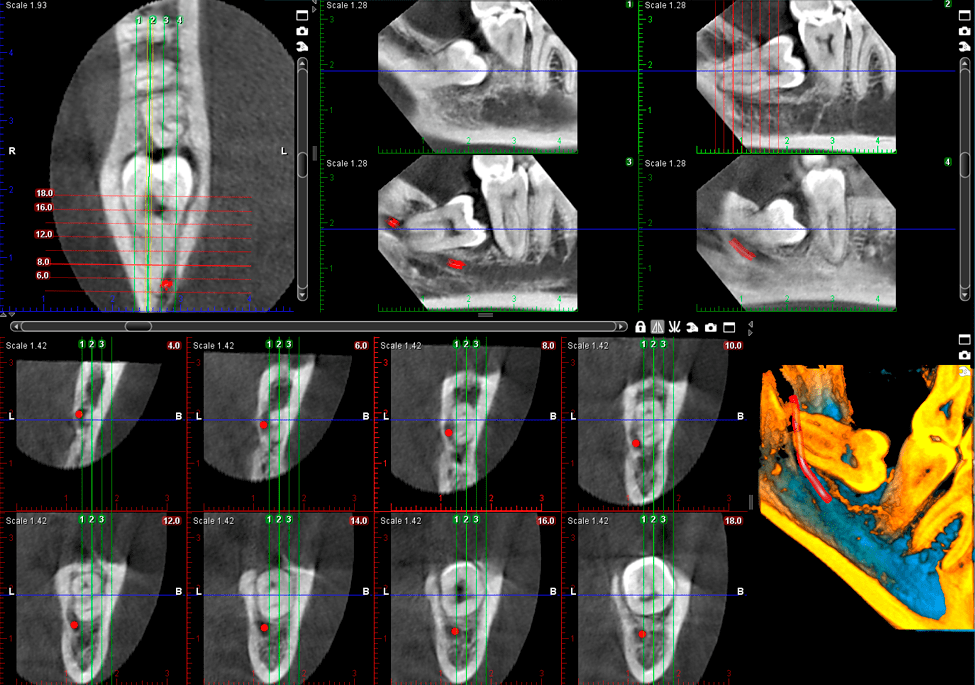

Naruszony kieł

8x8